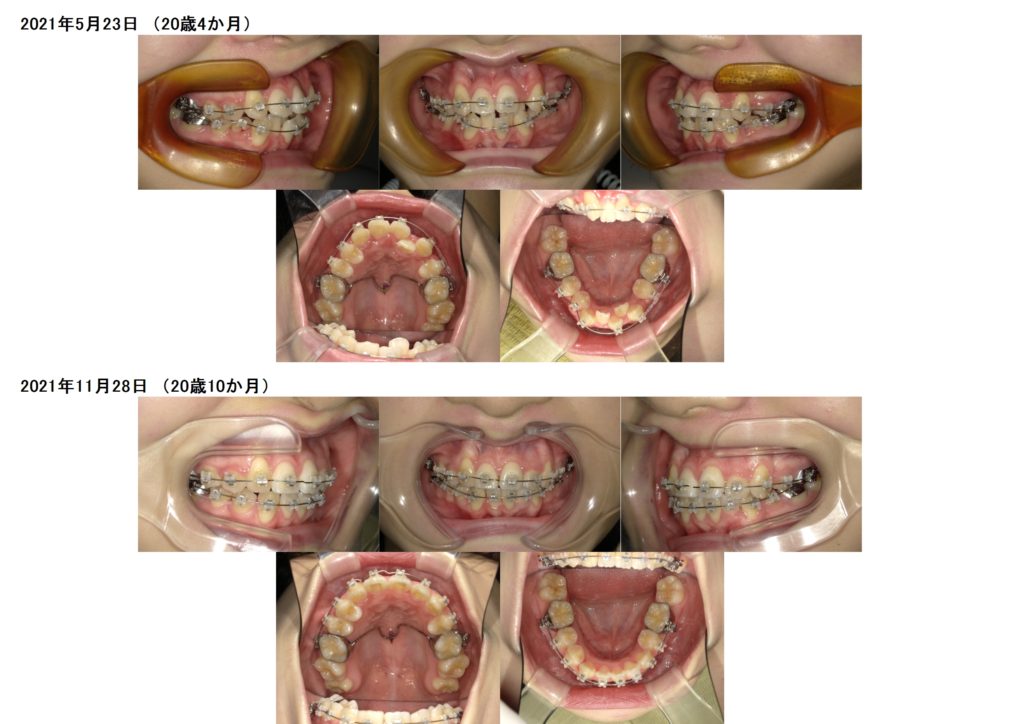

どんどん歯は動いていきます☆

とっても早いスピードですよね☺

最後に3カ月ほど、噛み合わせを整えるために顎間ゴムを使用しました。